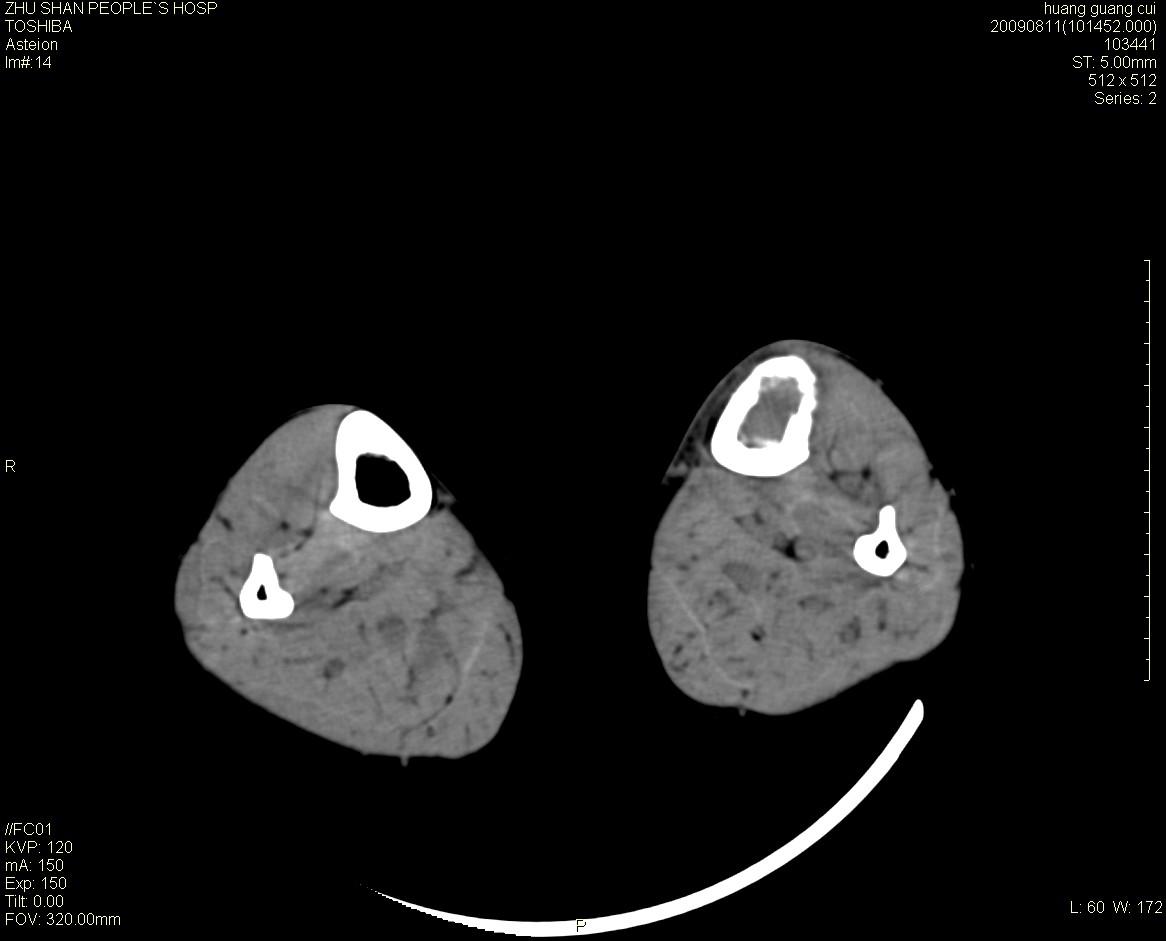

女性 56岁 左胫骨中断肿痛2月余。转移瘤or尤文氏肉瘤?

左侧胫骨中段骨皮质溶骨性破坏,髓腔内外见软组织肿块,无明显钙化及成骨,定位相显示病变周围“筛孔样”改变,定性恶性无疑,原发或转移均有可能,倾向于骨纤维肉瘤可能性大,转移瘤不排除。膝关节以下骨转移很少,且要有原发灶支持,尤文氏肉瘤年龄太大不支持。